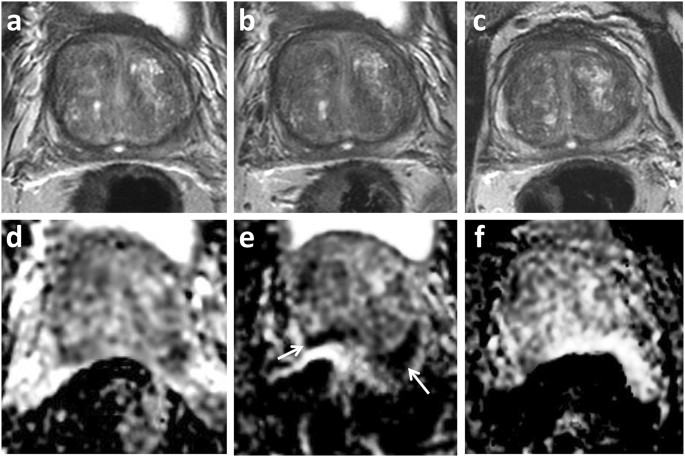

Distortion artefact in active surveillance. 66 year old patient on active surveillance. PSA 6.02 ng/ml at enrolment MRI 2014 (a,d), and stable at follow-up imaging in 2015 (b,e) and 2016 (c,f). Top row T2-weighted imaging, bottom row ADC maps. 2015 study included within current cohort shows posterior warping with apparent new and marked restricted diffusion (arrow), this is artefactual and not present on subsequent follow-up imaging.

The ability to map and quantify distortion on DWI is beneficial for assessment of novel techniques or post-processing steps aimed at reducing the degree of distortion. This will also be relevant for metal artefact reduction sequences in musculoskeletal imaging, intending to reduce in-plane artefacts and through-plane artefacts due to metal in an adjacent plane19. Knowledge of location and extent of distortion may additionally be helpful in a number of clinical settings. MRI is increasingly being used in biopsy naïve patients in order to identify lesions and target subsequent biopsy. DWI is seen as the key sequence for interpretation of the peripheral zone, where the majority of tumours are located, and is the secondary sequence for the transition zone. Although minor distortion may not affect the targeting of larger lesions20, knowledge of distortion will be necessary when outlining smaller targets. Focal therapy for prostate cancer is emerging as a management strategy for intermediate risk prostate cancer21. Herein, planning is often performed on pre-operative diagnostic MRI and accurate lesion delineation is essential to ensure adequate treatment coverage and a successful outcome22. MRI is increasingly being used in active surveillance protocols and imaging features suggesting lesion progression are used as either a trigger for repeat biopsy, or a switch to active therapy23. Distortion artefact in this scenario may mistakenly be assigned as MRI progression (Fig. 6) and could therefore lead to unnecessary intervention.